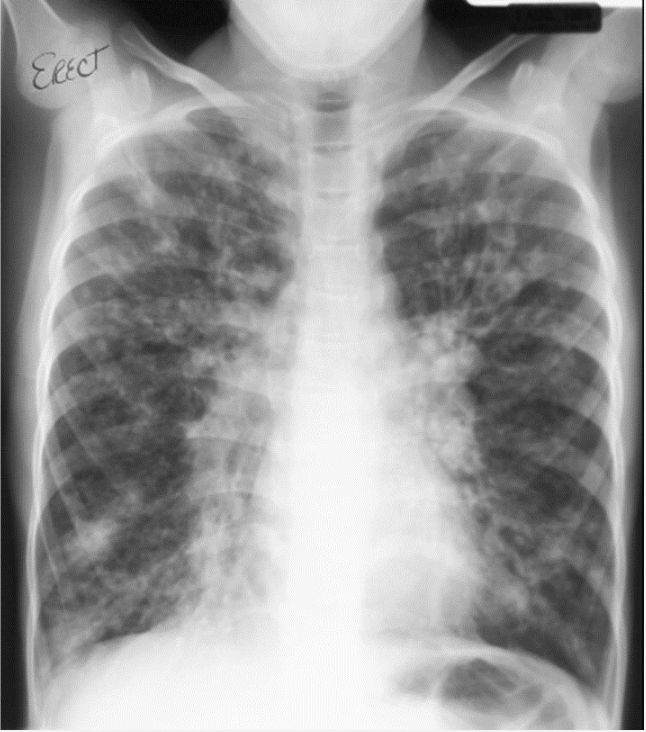

Acute respiratory distress syndrome

- normal heart

-no pleural effusion

-bilateral widespread pulmoonary inflitrates

-air bronchograms